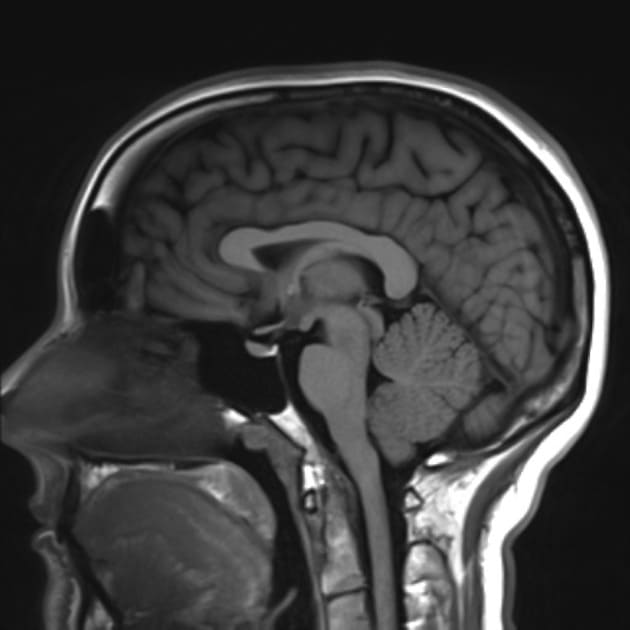

Признаки кисты на МРТ головного мозга

Основная задача МРТ головы при подозрении на кисту — выяснить, какова ее локализация, размеры, соответствует ли степень изменений и местоположения с теми неврологическими проявлениями, что имеются у пациента. Вторая задача томографии — дифференцировать кистозное образование от опухоли головного мозга, сосудов или оболочек. Здесь врач на МРТ снимках будет искать следующие признаки:

- шарообразное образование с круглыми четкими краями;

- признаки жидкости внутри капсулы кисты;

- отсутствие тканевой инвазии в соседние структуры головного мозга.

На снимках МРТ головного мозга кисты определяются с высокой долей вероятности. Они выглядят как темные с ровными границами округлые пятна. Поскольку злокачественные раковые образования на изображениях во многом схожи с кистозными, для определения природы новообразования , зачастую, используют контрастное вещество. За счет отсутствия сосудистых структур кисты не накапливают контраст и после его введения затемненная область так и остается темным пятном с ровным контуром.